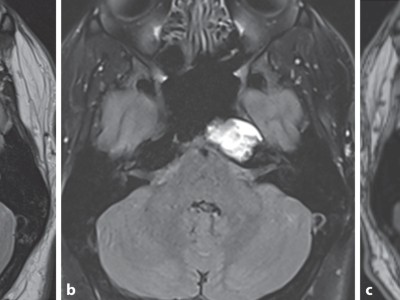

Bei einer einseitigen Verschattung der Nasennebenhöhlen kommen zahlreiche benigne und maligne Differenzialdiagnosen in Frage. Oft ergibt erst die Histologie die richtige Diagnose, wie in diesem Fall eines 32-Jährigen mit rezidivierender Epistaxis, Rhinorrhoe und Druckgefühl auf dem linken Auge.